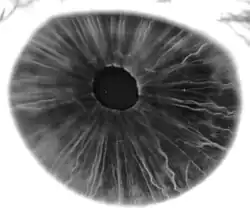

-

Iris, front view -